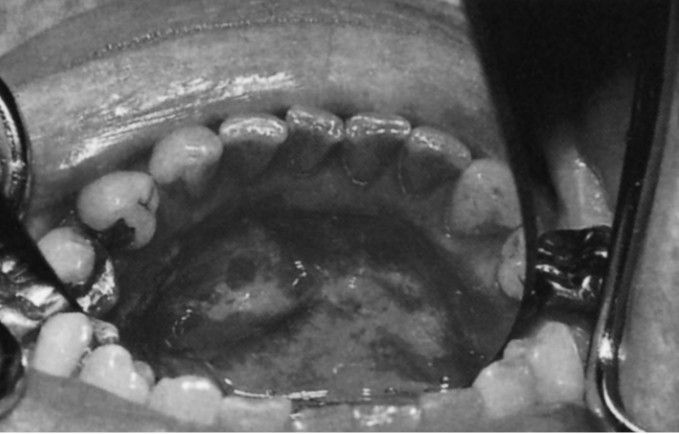

Irregular leukoplakia involves the floor of the mouth and extends to the attached gingiva of the lingual aspect of the mandible. Histopathologic interpretation was of severe dysplasia with areas of carcinoma in situ; no invasion of connective tissue was seen.